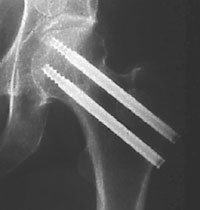

I den første registreringsperioden (gruppe A) ble det brukt to AO Hip Pin, Stratec Medical (fig 1). Dette er kanylerte skruer uten hode. Gjengediameteren er lik skaftdiameteren på 6,5 mm. I den påfølgende registreringsperioden (gruppe B) ble det brukt to AO 7,3 mm Cannulated Screws, Stratec Medical (fig 2). Dette er skruer med hode, gjengediameteren er 7,3 mm og skaftdiameteren 4,5 mm (tab 1).